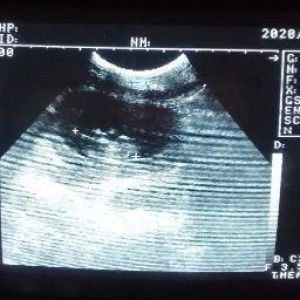

8 weeks pregnant,normal po ba ang pananakit ng balakang, at parang mabigat na puson?

8weeks pregnant